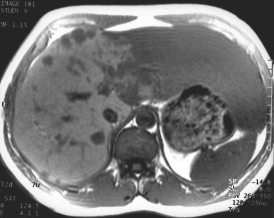

Ce patient est porteur d'angiomes multiples dont un angiome géant du lobe gauche

L'aspect est ici caractéristique, franchement hyper T2 et hypo T1 Prise de contraste en motte très denses. La totalité de l'angiome fini par se remplir sur les coupes très tardives.